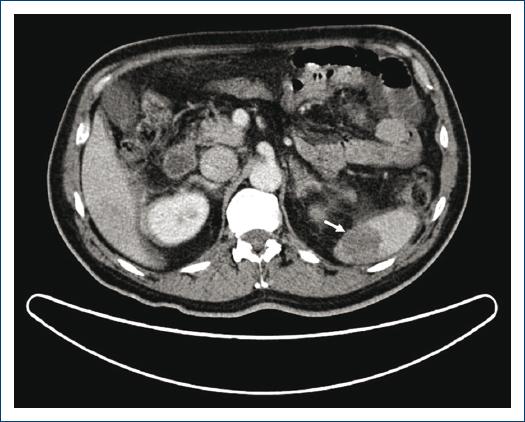

Con posterioridad, el paciente permaneció estable desde el punto de vista cardiológico, sin desarrollar insuficiencia cardíaca ni episodios arrítmicos. En las primeras 24 horas, el paciente comenzó con fiebre y dolor abdominal a nivel del flanco izquierdo de difícil control sintomático, por lo que se solicitó estudio de imagen abdominal mediante tomografía computarizada, que diagnosticó infarto esplénico (Fig. 2), así como trombosis de un radical venoso de la vena suprahepática media. Además, se identificó un aumento del perímetro del miembro inferior izquierdo con elevación del calor local y eritema de éste. El estudio Doppler de miembros inferiores demostró otro episodio trombótico en un ramo venoso perforante muscular. Dada la persistencia de la fiebre y el aislamiento en sangre de grampositivos (P. acnes), se realizó una TEP-TAC que delineó un defecto de perfusión segmentario en el lóbulo superior derecho consistente con embolia pulmonar, y se descartó un proceso infeccioso en el material protésico intraaórtico. Ante estos hallazgos se incrementó la dosis administrada de fondaparinux hasta 7.5 mg al día por vía subcutánea, sin nueva recurrencia de episodios tromboembólicos, y recuperación progresiva de cifras plaquetarias hasta 159,000/μL (la cifra más baja registrada fue de 32,000 plaquetas/μL). Por último, el paciente egresó con acenocumarol y tratamiento antiagregante con ácido acetilsalicílico (100 mg al día). Se indicó seguimiento posterior en consultas de los Servicios de Cardiología y Hematología, sin notificación de nuevos episodios isquémicos y con retiro de la anticoagulación oral luego de 12 meses de tratamiento.

Figura 2 Hallazgos intraabdominales por tomografía axial computarizada que demuestran infarto esplénico (flecha).